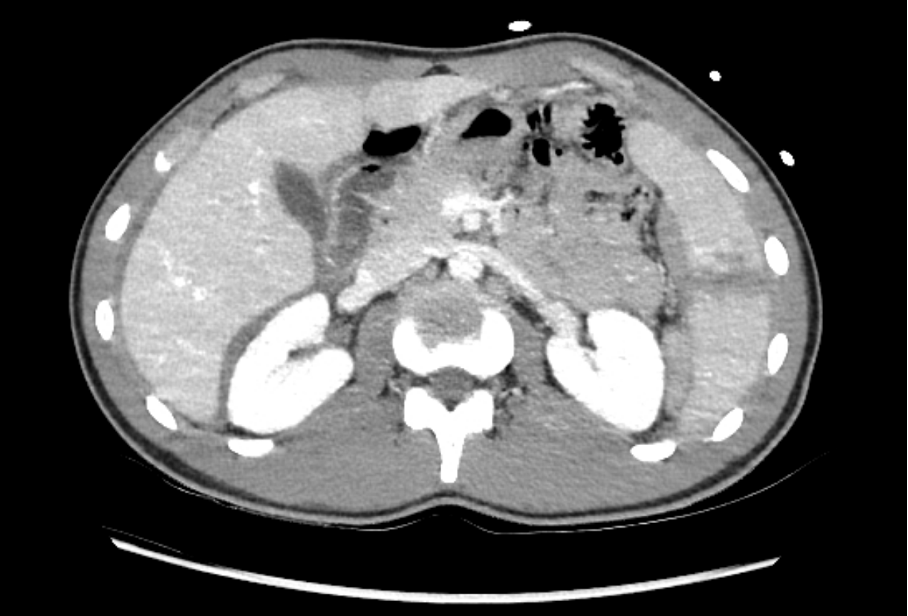

L’échographie POCUS E-FAST retrouve uniquement une lame de liquide libre péri-hépatique et péri-splénique avec une plage hypodense au pôle inférieur de la rate.

Le rapport du CT thoraco-abdominal fait état de lacérations post-traumatiques spléniques étendues classées grade IV selon AAST (cf tableau 2), atteignant le hile splénique, associées à un probable hématome sous capsulaire splénique médial et un saignement actif veineux au sein de lacération, un hémopéritoine abondant de localisation péri hépatique, péri splénique ainsi que dans le petit bassin et du liquide libre de densité hématique au sein de la gouttière pariéto-colique gauche.